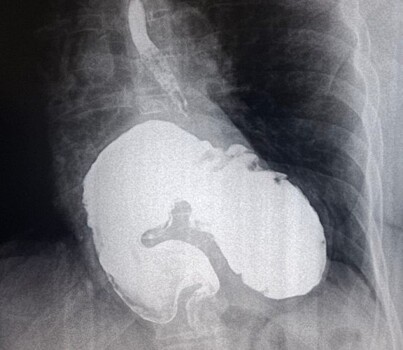

В ККБ №2 при проведении стандартного обследования, рентгеноскопии пищевода, желудка и двенадцатиперстной кишки, у пациентки была выявлена редкая патология.

У женщины, которая наблюдалась у кардиолога с жалобами на одышку и боли в сердце, обнаружили гигантскую грыжу пищеводного отверстия диафрагмы.

Данные состояния могут развиваться бессимптомно или маскироваться под другие заболевания.

После диагностики пациентка была направлена на консультацию к хирургам и сейчас проходит лечение в стационаре. Этот случай подчеркивает необходимость регулярных обследований, даже при отсутствии явных симптомов, напомнили медики.